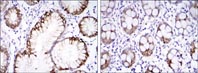

Immunohistochemistry (Formalin/PFA-fixed paraffin-embedded sections) - Alexa Fluor® 647 Anti-Carbonic Anhydrase 9/CA9 antibody [EPR4151(2)] (AB225074)

IHC image of Carbonic Anhydrase 9/CA9 staining in a section of formalin-fixed paraffin-embedded normal human stomach*.

The section was pre-treated using heat mediated antigen retrieval with sodium citrate buffer (pH6, epitope retrieval solution 1) for 20mins performed on a Leica BOND™. Non-specific protein-protein interactions were then blocked in TBS containing 0.025% (v/v) Triton X-100, 0.3M (w/v) glycine and 1% (w/v) BSA for 1h at room temperature. The section was then incubated overnight at +4°C in TBS containing 0.025% (v/v) Triton X-100 and 1% (w/v) BSA with ab225074 at 1/100 dilution (shown in red) and counterstained using ab195887, Mouse monoclonal to alpha Tubulin (Alexa Fluor® 488), at 1/250 dilution (shown in green). Nuclear DNA was labelled with DAPI (shown in blue). The section was then mounted using Fluoromount®.

Image was taken with a confocal microscope (Leica-Microsystems, TCS SP8).